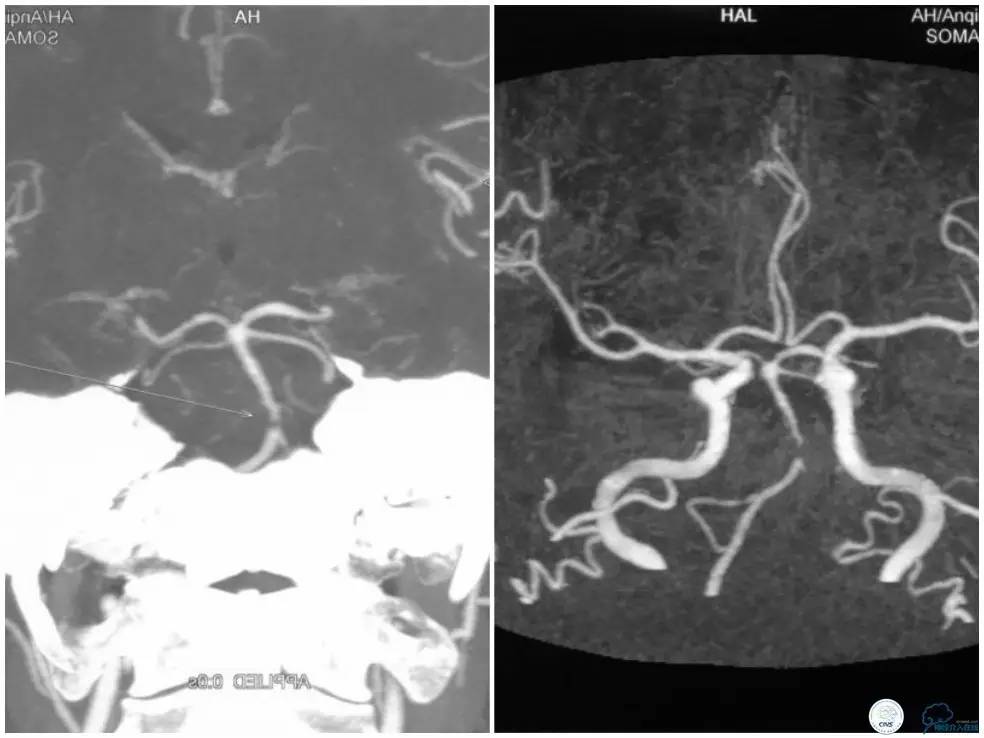

CTA示基底动脉重度狭窄(图3)。

图3

入院后查高分辨核磁提示(图4):基底动脉起始处管腔内壁环形增厚,斑块形成,内壁粗糙,形态不规则,斑块呈等T1信号,增强后斑块呈明显均匀强化。DWI序列上未见明显弥散受限病灶。考虑诊断基底动脉起始处管壁斑块形成,表面溃疡形成。

图4